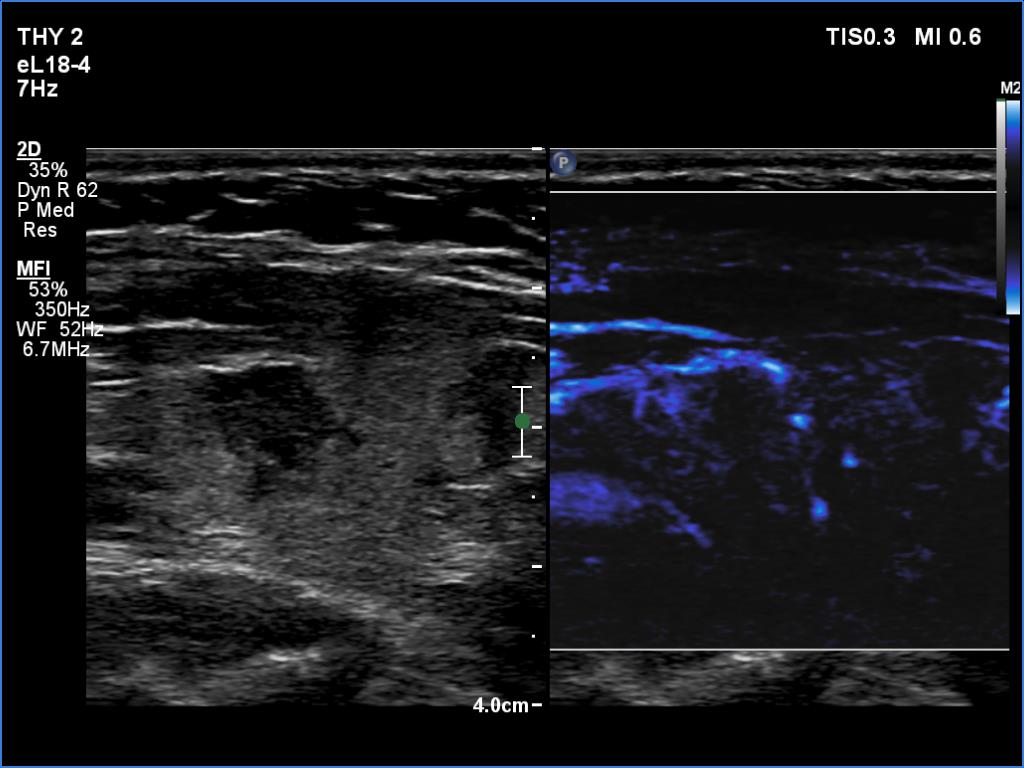

Left lobe, longitudinal scan, microflow imaging. The pattern is not specific.